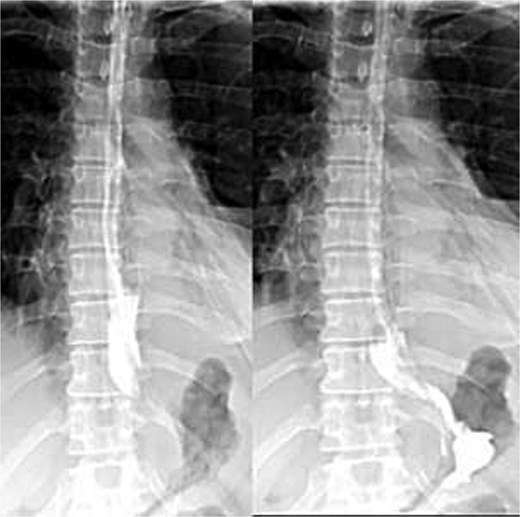

Enteral feeding via nasogastric tube began on day 2 and was well tolerated. A Gastrografin esophagogram on day 5 showed free flow of contrast without leakage; (Fig. 3) the nasogastric tube was removed, and oral intake advanced. By day 7, the chest drain was removed, and the patient was discharged.

Postoperative Gastrografin esophagogram on day 5 showing free contrast flow without leakage.